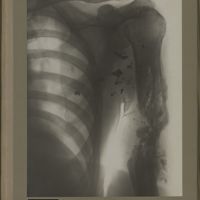

0179 - Page 67 - [Radiographies du thorax]0179 - Page 67 - [Radiographies du thorax]